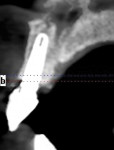

Following the technique for immediate extraction, immediate implant placement and provisionalization procedures outlined previously, the patient had teeth Nos. 7 through 9 removed by atraumatic, minimally invasive means, debridement was accomplished, and 3 implants were placed: a NobelActive implant (Nobel Biocare, nobelbiocare.com) measuring 3.5 mm x 11.5 mm at No. 7; and 2 NobelActive implants measuring 3.5 mm x 13.5 mm placed at Nos. 8 and 9 respectively, with each implant obtaining an ISQ of 50 Ncm at placement. Implant placement was accomplished by a minimally invasive (flapless) protocol. Reconstruction of the missing buccal plate in the region of teeth Nos. 7 through 9 was accomplished once again by an allogenic, mineralized, cancellous 1-mm to 2-mm-particle-size bone graft (LifeNet Health, lifenethealth.org) condensed into the peri-implant defects, to the level of the crest of the bone-level NobelActive implant (Figure 16). Provisional QuickTemp Abutment Conical Connection (Nobel Biocare) were screwed into place, and an immediate provisional restoration constructed from the retrofitted TempStent II surgical guide32 provisionalization system. The provisional restoration was cemented with Temp-Bond™ Clear (Kerr, kerrdental.com), and the excess cement was removed. The patient was allowed to follow a 3-month healing and observation period after which fixture-level impressions were obtained and computer-aided design and computer-aided manufacturing custom-milled zirconia abutments were constructed. This was followed by a second set of provisional restorations the patient utilized for an additional 2 months. Final impressions were taken of the zirconia abutments, and final all-ceramic restorations were constructed and cemented into place. The case’s complete clinical view can be seen in Figure 17. Figure 18 shows the 4.5-year post-treatment clinical view, while Figure 19 shows the 4.5-year post treatment computed tomography (CT) scan serial view. Please note that the total reconstruction of the buccal bone structures achieved by the minimally invasive bone graft procedure was accomplished following the technique previously outlined.

A 49-year-old nonsmoking male presented for treatment of his advanced tooth loss, terminal dentition, residual infection after dental treatment, and recurrent sinus infections. His dental history consisted of multiple attempts at conventional treatment approaches to prolong tooth longevity, several implant procedures to replace failing endodontically treated teeth and edentulous sites (all resulting in repeated failure of treatment), compromised esthetics, and various secondary infectious diseases related to previous failures of dental treatment. The pretreatment CT scan view of the maxillae and several serial views (Figure 20) demonstrated multiple edentulous sites, residual sinus infections, failing implant procedures with large alveolar defects, and the remaining dentition, which can be classified as a “terminal dentition.” After reviewing multiple treatment options with the patient ranging from conventional fixed and removable options, to partial implant reconstruction with extensive bone replacement procedures recommended, the patient opted for removal of most of the remaining dentition, correction of sinus pathology, multiple implant placement, and immediate provisionalization procedures, most accomplished by a conservative, minimally invasive protocol (except for the sinus regions, which required flap access and a lateral-wall osteotomy), and immediate loading of the implants at the initial and only surgical procedure planned. After extensive medical and dental histories were taken, medical clearance for the preexisting sinus infections was obtained, and a complete dental workup consisting of a facebow transfer, mounted maxillary and mandibular pretreatment models, a complete diagnostic waxup of both the hard and soft tissues required to be replaced, and construction of the TempStent II surgical guide and provisionalization system, the patient was given an appointment for the complex surgical visit. During this surgery, remaining dentition and implants were removed, ten implants in the maxillary arch were inserted, and bilateral sinus elevations and alveolar reconstruction was performed along with peri-implant bone grafting and immediate provisionalization. In the mandibular arch, removal of the remaining dentition was done, except for teeth Nos. 21, 22, 27, and 28, and six implants were placed and immediately provisionalized, keeping the patient in the planned first-molar occlusion scheme. The immediate post-treatment panoramic view can be seen in Figure 21. After an uneventful healing for 4.5 months, the patient then initiated the final reconstructive phase of his treatment. A 7-year post-treatment clinical view can be seen in Figure 22, with the 7-year post-treatment CT panoramic scan, axial and serial views of the maxillary central incisor seen in Figure 23.